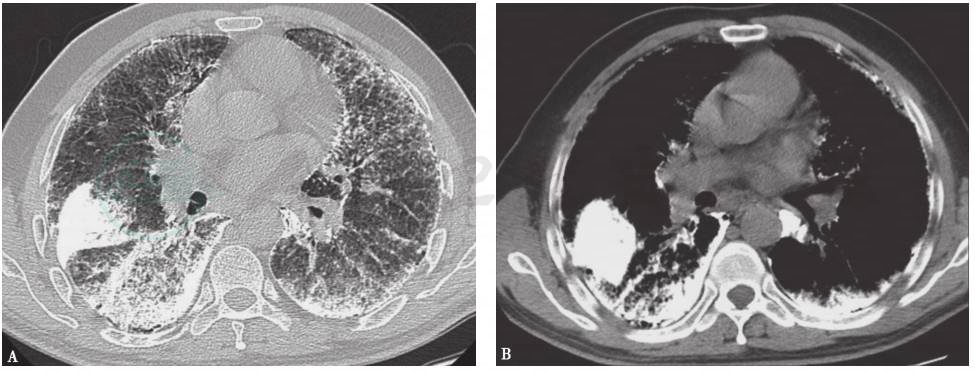

图3 肺泡微结石症胸部影像学表现

胸部CT可见双肺野弥漫高密度影,伴双肺实质钙化,以坠积部位为主,并见胸膜钙化线和胸膜下小气囊征

肺泡微结石症:是以肺泡内存在弥漫性分布钙化的含钙、磷盐为主的微小结石为特点的弥漫性肺疾病,是一种隐性遗传性疾病。该病主要是由于SLC34A2基因突变,导致磷酸钙清除障碍,使之在肺泡内沉积形成。患者早期多无明显症状和体征。一般血液检查显示钙磷代谢无异常改变。胸部CT可见两肺弥漫性钙化结节影,随着病情进展可融合成高密度片状影(图3)。病理检查可见肺泡内含有洋葱皮样物体,大部分呈致密钙化。该病临床确诊较为容易,经支气管镜和胸部CT检查大多可明确。本例患者家族无相关疾病病史,患肺泡微结石症可能性较小,可进一步完善支气管镜检查以协助诊断。